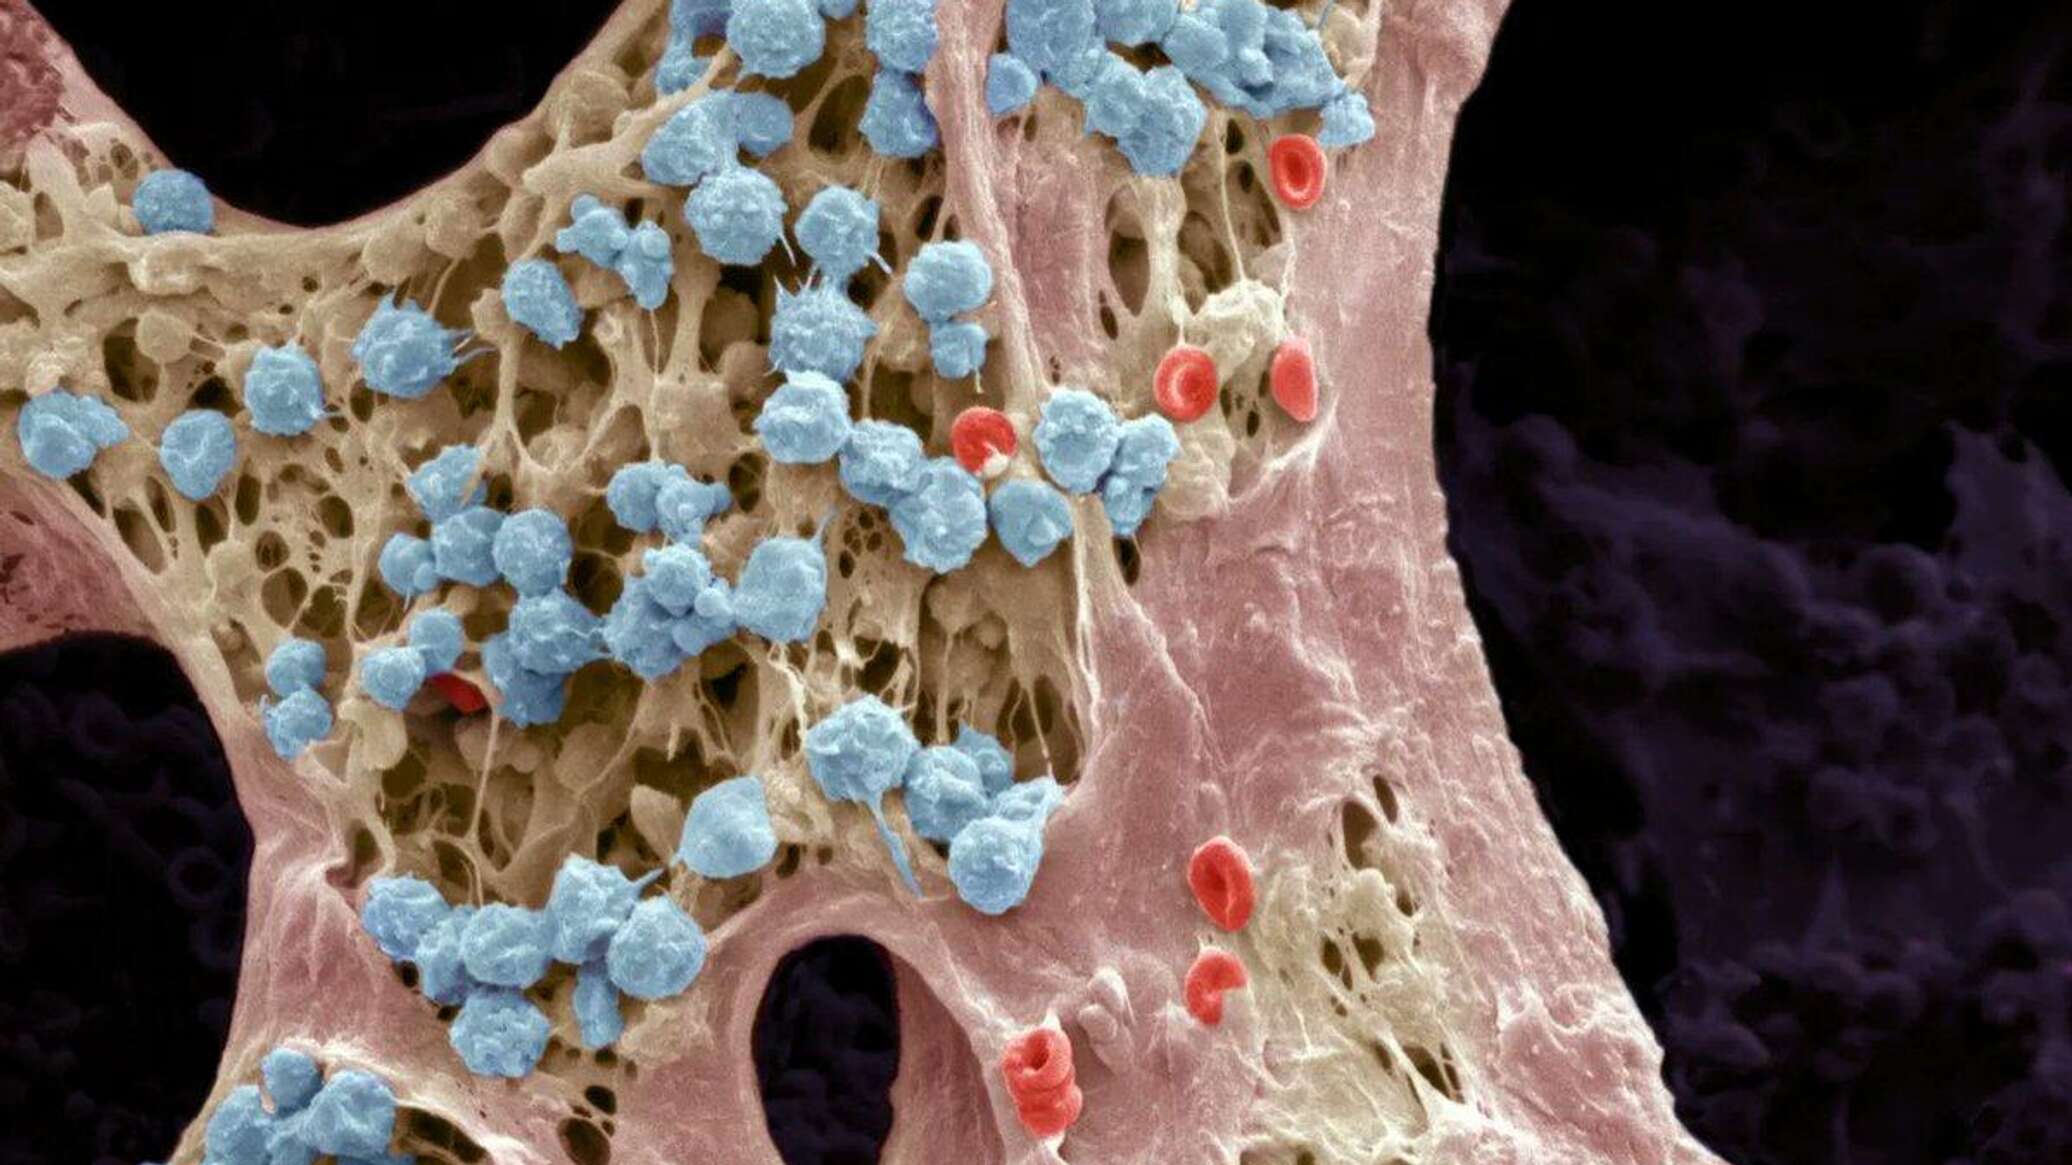

Изучение костного мозга: анатомия и функции